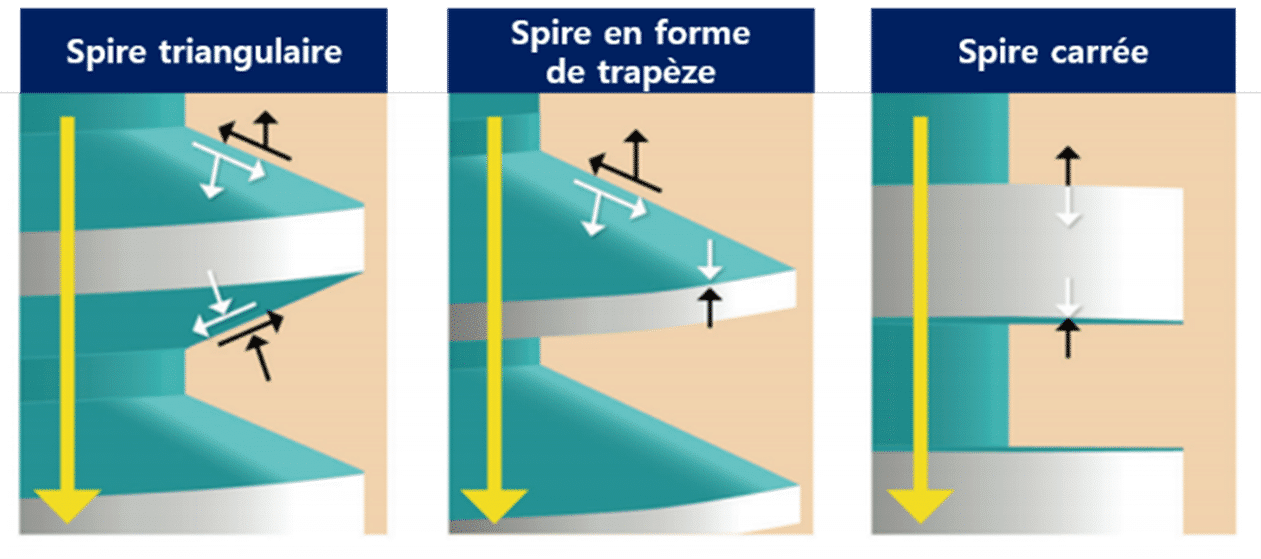

La caractéristique la plus intéressante du Magic Fin Thread est la forme carrée de son extrémité.

Lorsqu’une spire à extrémité triangulaire est insérée dans l’os de la mâchoire, cela entraîne inévitablement des forces de compression, de traction et de cisaillement. Cependant, par rapport à une spire triangulaire, une spire carrée présente des forces de cisaillement et de traction nettement inférieures, et transmet principalement les forces sous forme de compression.

Alors que l’os de la mâchoire présente généralement une résistance plus élevée aux forces de compression, les forces de cisaillement sont la principale cause de micro-fractures. Par conséquent, le Magic Fin Thread peut réduire considérablement le risque de micro-fractures entre l’os de la mâchoire et l’implant (figure 11).

(Figure 11) Propriétés physiques selon la forme des spires.